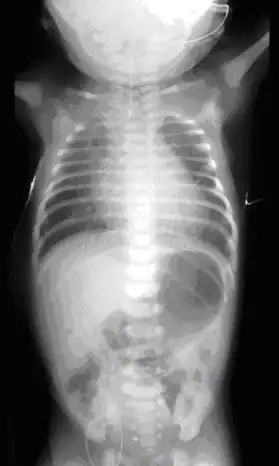

El diagnóstico de una atresia de esófago ocurre casi siempre posnatal con la sospecha en caso de polihidramnios o en casos en donde la maniobra de inserción de la sonda nasogástrica u orogástrica del recién nacido en la sala de partos no supera los 10 cm desde la arcada dentaria hasta el cardias estomacal. De no hacerse esta maniobra al recién nacido, se observará más tarde que el bebé presenta hipersalivación, dato que pone en sospecha un probable esófago a fondo ciego que no permite que la saliva pase al estómago. Una radiografía de tórax y abdomen con contraste revela de inmediato la presencia del saco esofágico.